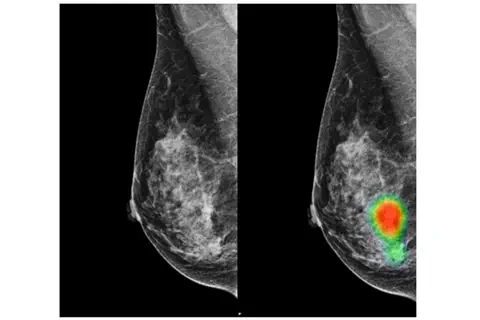

Les radiologues assistés par l'IA peuvent détecter davantage de cancers du sein avec une réduction des rappels de faux positifs

Lunit, le 11/02/2020 : SÉOUL, Corée du Sud, 11 février 2020 /PRNewswire/ -- Une nouvelle étude, publiée dans la revue Lancet Digital Health, souligne la valeur ajoutée de la détection du cancer du sein assistée par l'IA à partir d'images mammographiques. […].